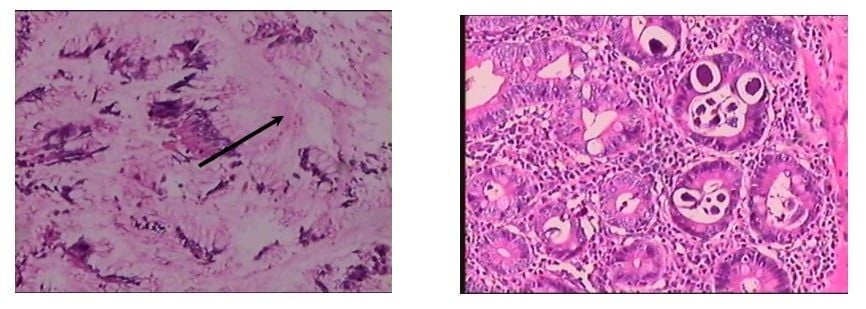

A: Hình ảnh viêm loét dạ dày – B: Hình ảnh giun lươn (Mũi tên) trong ruột non

Tuy nhiên, kết quả bất ngờ nằm ở mẫu mô sau khi phẫu thuật. Khi soi dưới kính hiển vi, các bác sĩ Giải phẫu bệnh đã phát hiện ra "thủ phạm" thực sự: Giun lươn đang ký sinh trong niêm mạc ruột non, hoàn toàn không có tế bào ung thư như nghi ngờ ban đầu.